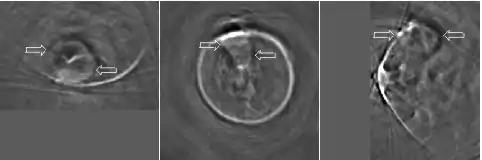

Thermoacoustic imaging was originally proposed by Theodore Bowen in 1981 as a strategy for studying the absorption properties of human tissue using virtually any kind of electromagnetic radiation.[1] But Alexander Graham Bell first reported the physical principle upon which thermoacoustic imaging is based a century earlier.[2] He observed that audible sound could be created by illuminating an intermittent beam of sunlight onto a rubber sheet. Shortly after Bowen's work was published, other researchers proposed methodology for thermoacoustic imaging using microwaves.[3] In 1994 researchers used an infrared laser to produce the first thermoacoustic images of near-infrared optical absorption in a tissue-mimicking phantom, albeit in two dimensions (2D).[4] In 1995 other researchers formulated a general reconstruction algorithm by which 2D thermoacoustic images could be computed from their "projections," i.e. thermoacoustic computed tomography (TCT).[5] By 1998 researchers at Indiana University Medical Center[6] extended TCT to 3D and employed pulsed microwaves to produce the first fully three-dimensional (3D) thermoacoustic images of biologic tissue [an excised lamb kidney (Fig. 1)].[7] The following year they created the first fully 3D thermoacoustic images of cancer in the human breast, again using pulsed microwaves (Fig. 2).[8] Since that time, thermoacoustic imaging has gained widespread popularity in research institutions worldwide.[9][10][11][12][13][14][15] As of 2008, three companies were developing commercial thermoacoustic imaging systems – Seno Medical,[16] Endra, Inc.[17] and OptoSonics, Inc.[18]

Microwaves have also been used to form 3D thermoacoustic images of the human breast. One of the first devices to do so is depicted in Fig. 10. It consisted of an array of eight waveguides, which directed microwave energy into the breast. A transducer array was rotated in synchrony with the waveguides in order to acquire sufficient data to reconstruct the internal structures of the breast. Figure 11 shows an animation of the typical glandular tissue pattern in a normal breast.